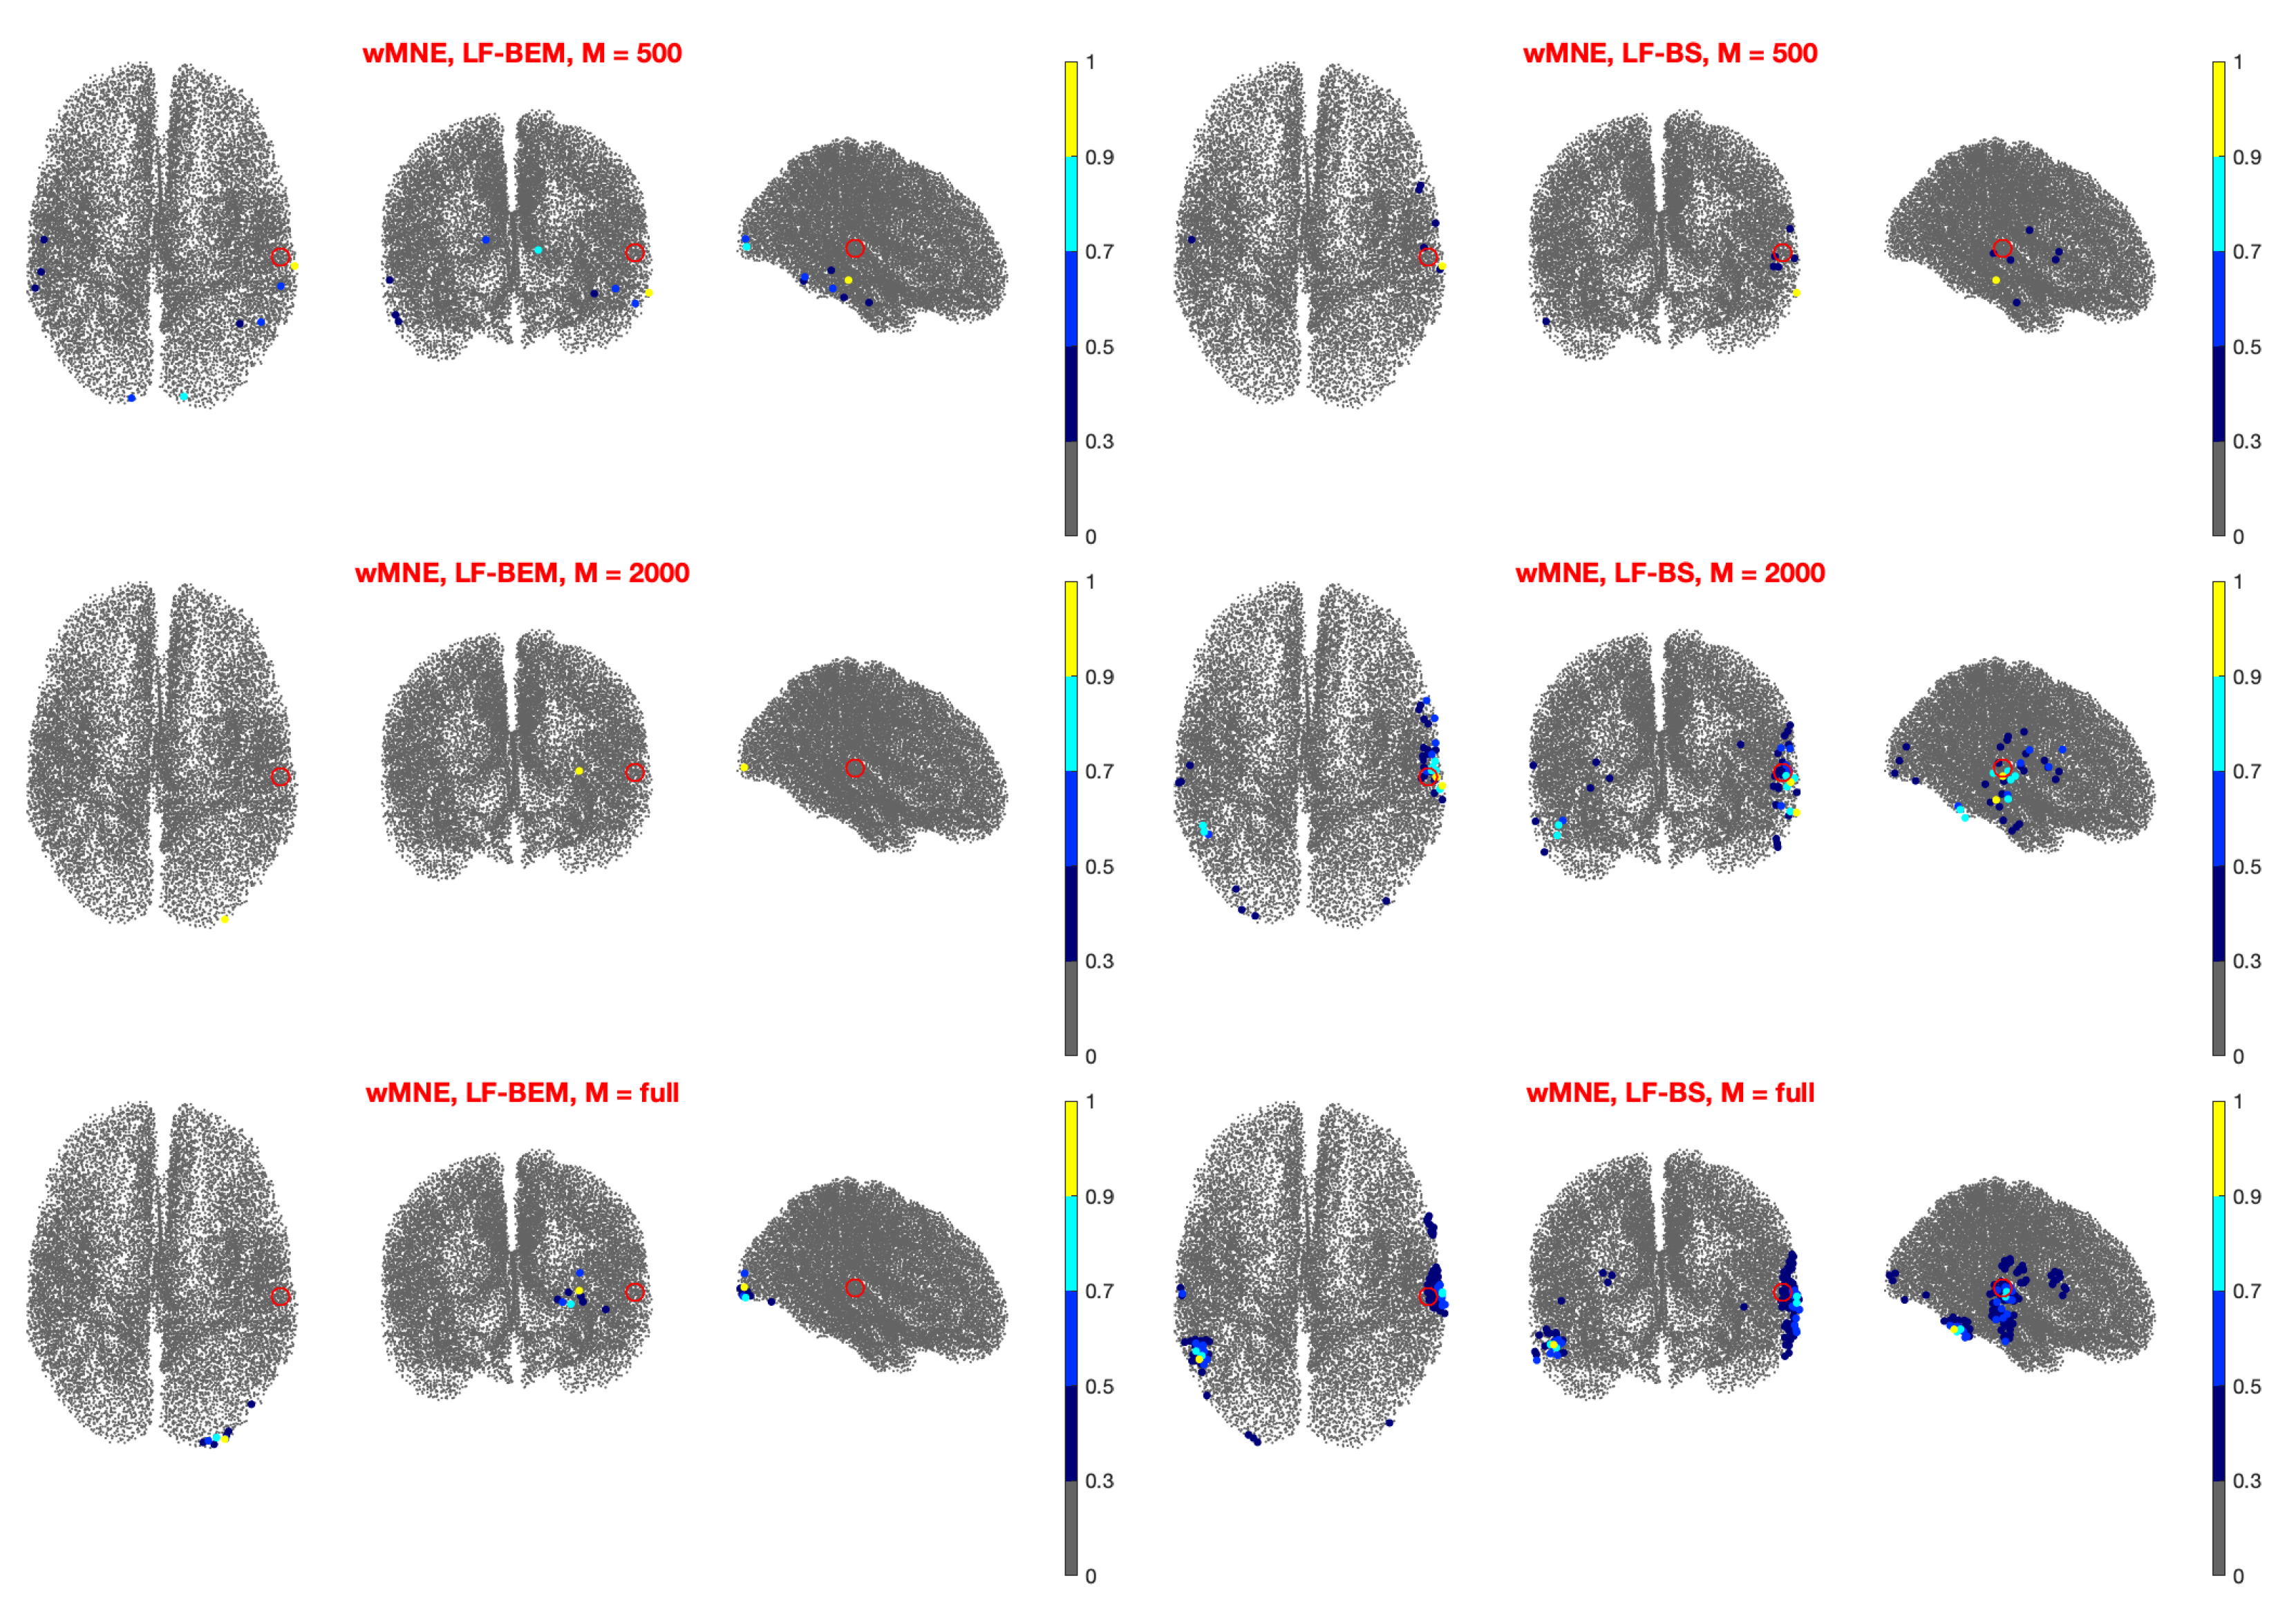

3.2. Real Data Analysis

- Left Auditory Case (Figure 2): The random sampling method with gives lower errors when using LCMV or TSBF as inversion methods. In particular, for the DLE is about 1 cm or less when they are coupled with LF-BS. As for the other inversion methods, LSQR produces a slightly higher DLE, i.e., below 2 cm, while wMNE and dSPM produce a DLE greater than 2 cm. As expected, the DLE decreases when M increases except for wMNE, which is the less accurate inversion method. Nevertheless, the decrease is very small for .